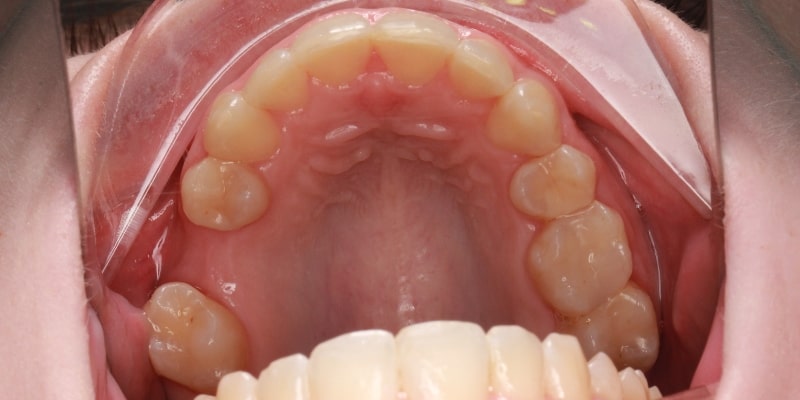

Stłoczone zęby i krwawiące dziąsła — problem pacjentki

Pacjentka zgłosiła się do naszego gabinetu dentystycznego Tłuczewicz Dental Studio w Warszawie, ponieważ chciała poprawić estetykę swojego uśmiechu. Głównym problemem, który wpływał na jej pewność siebie i utrudniał codzienną higienę, były znaczne stłoczenia zębów. Taki stan często prowadzi do dalszych komplikacji, dlatego leczenie krzywych zębów było w tym przypadku priorytetem. Dodatkowo badanie wykazało problem krwawiących dziąseł, co wymagało natychmiastowej interwencji jeszcze przed rozpoczęciem leczenia ortodontycznego.

Efekty leczenia nakładkami były widoczne już po kilku miesiącach. Aparat nakładkowy skutecznie zlikwidował stłoczenia, a zęby ustawiły się w idealnie równym łuku. Metamorfoza uśmiechu pacjentki była spektakularna – odzyskała nie tylko piękny wygląd, ale również zdrowie i komfort.